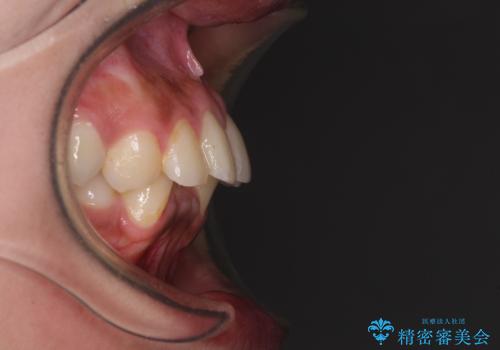

深い咬み合わせと前歯のデコボコ インビザラインによる矯正治療

- 前歯のデコボコと、食いしばりやすい咬み合わせを気にして来院された患者様です。

骨格的に下顎骨が左側に偏位しており、インビザラインでの矯正治療では奥歯の咬みにくさが残る仕上がりが懸念されましたが、新幹線での通院となるため、来院回数の少ないインビザラインでの治療を希望されました。

一方で、デコボコや下顎の前歯が隠れてしまうほどの深い咬み合わせはしっかりと改善されました。